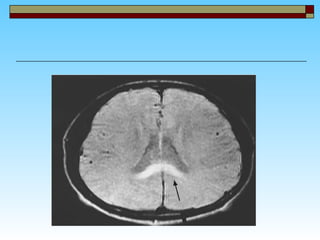

In HACE,All are true EXCEPT: Characterized by evidence of global cerebral dysfunction  symptoms of severe AMS & HAPE are usually present  It is uncommon with 10-20% incidence MRI of patients with HACE reveals white matter changes consistent with vasogenic edema

In HACE,All aretrue EXCEPT: Characterized by evidence of global cerebral dysfunction symptoms of severe AMS & HAPE are usually present It is uncommon with 10-20% incidence MRI of patients with HACE reveals white matter changes consistent with vasogenic edema